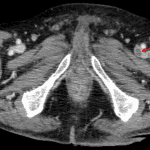

Indication: Left flank pain

- 13 mm proximal left ureteral calculus with associated severe left hydroureteronephrosis and severe renal cortical thinning

- Multiloculated fluid and gas collection in the left perinephric space with posterior rupture/extension into the posterior pararenal space and left flank soft tissues measuring 15 x 13 x 30 cm

- Nonocclusive filling defect in the left femoral vein

- Possible additional nonocclusive filling defect in the right femoral vein

- Perinephric abscess

- Deep venous thrombosis

Obstructing 13 mm proximal left ureteral calculus with resultant severe left hydronephrosis, severe left renal cortical thinning, and a large multiloculated left perinephric abscess which extends into the left flank soft tissues. A nuclear medicine renogram could be considered to assess differential renal function if this will impact the decision for surgical management.

Nonocclusive left, and possibly right, femoral deep venous thrombosis.